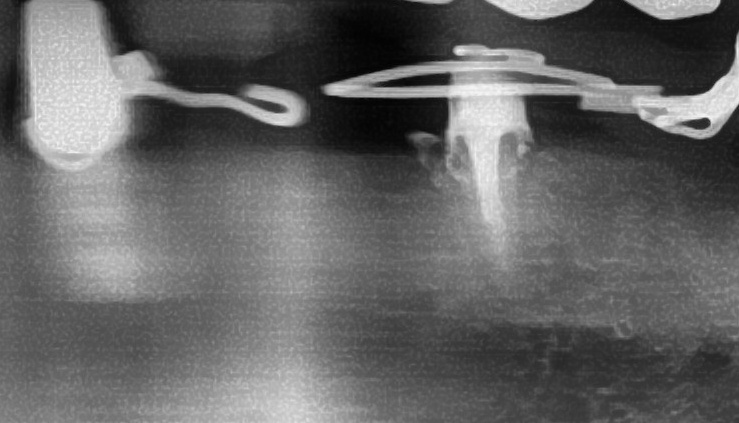

しっかりとインプラント埋め込まれた後は、動揺がないか、噛んだ時に当たらないかなどを確認して、最後にパノラマ写真を撮影して今回のオペは終了となりました。